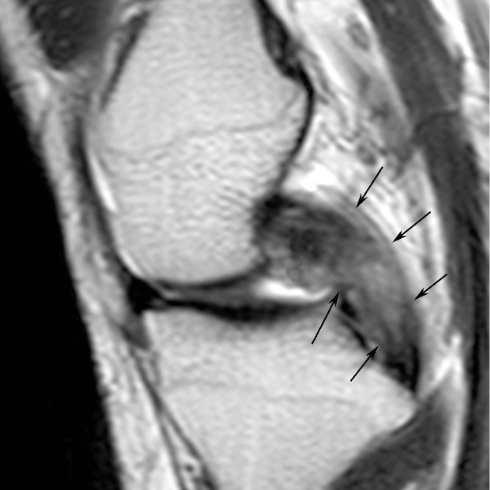

正常的韧带和肌腱在T1WI及T2WI上均表现为条带状低信号影,边缘清楚光滑,在不同体面成像时可显示其完整或斜行或断面的影像。损伤的韧带和肌腱,由于出血和炎性水肿,内可见高信号,尤其在T2WI上信号明显增高(图9)。根据损伤程度,可分为挫伤、部分断裂和完全断裂。挫伤表现为单纯的肿胀,但连续性仍完整;部分断裂表现为肌腱和韧带肿胀,其内出现横行线状或不规则的高信号影,但仍可见部分低信号的纤维影保持连续性;完全断裂则表现为肌腱和韧带连续性完全中断,断端可回缩,断裂处可为血肿或炎性组织填充。可合并肌腱、韧带附着处的撕脱骨折。关节附近的韧带损伤常合并关节内出血或积液。

图9 矢状位T2WI示后交叉韧带增粗、信号升高。